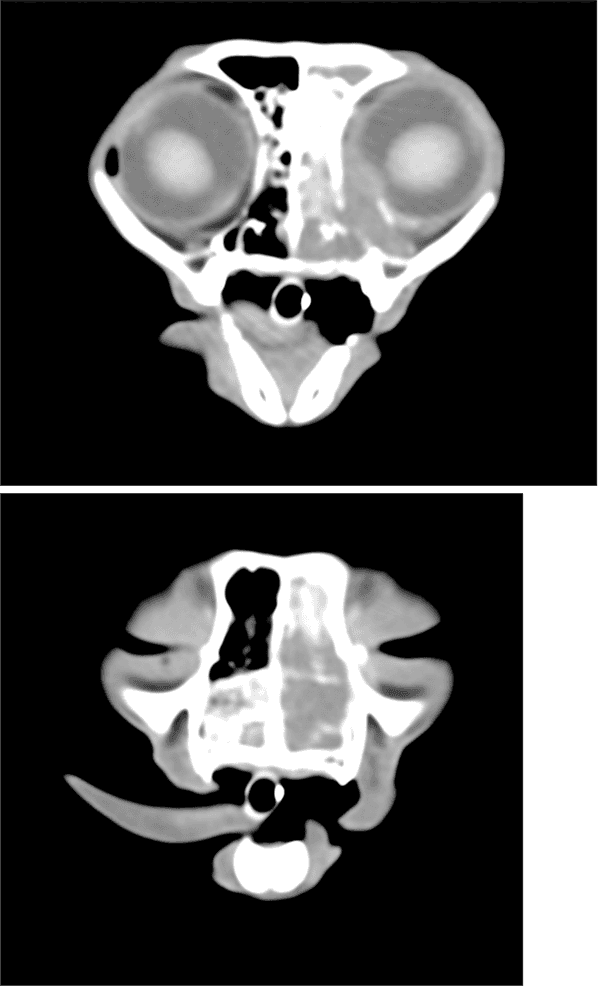

第5病日より放射線治療を実施した。照射プロトコルは1回8Gy 週1回 合計4回照射 総線量32Gyとなった 放射線治療の終了後、治療評価のためCT撮影を実施した。照射後CTでは大部分の病変は消失しているが、一部でびまん性病変の残存が疑われた。(図2)以上の所見より、放射線治療後残存したリンパ腫に対して化学療法を実施した。化学療法プロトコルは改変型COP療法とし、3ヵ月間継続した。治療後の経過は良好であり、現在化学療法終了から1年3ヵ月経過するが再発や転移は認められず、寛解を維持している。